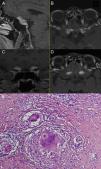

Isolated neurosarcoidosis (INS), as a disease of low prevalence, is commonly overlooked in differential diagnosis, and its discovery on histopathological examination usually comes as a surprise. Preoperative diagnosis is difficult because the clinical picture of INS is non-specific. Its symptoms depend on the location of the lesions, and the MRI results are similar to those found in meningiomas or optic nerve gliomas. Although up to 5% of all sarcoidosis patients present with neurological symptoms, those with INS are exceptionally infrequently encountered.

Three cases of INS are presented here, analysing their clinical course and radiological images, in order to determine characteristic traits that might lead to a correct diagnosis.